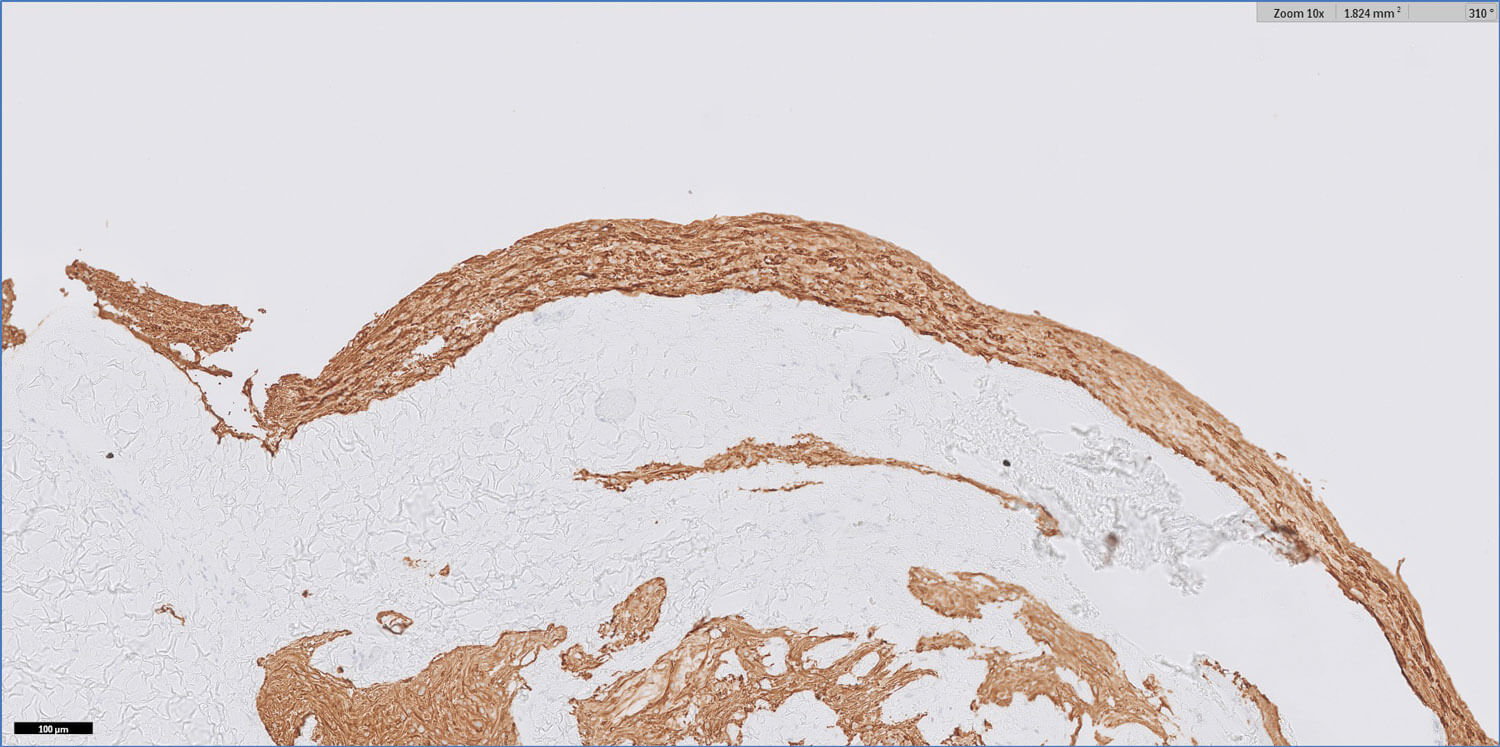

Figure 3: GFAP 10x.

Figures 1-3 show representative H+E-stained sections and glial fibrillary acidic protein (GFAP) immunohistochemistry of the lesion.

- Figures 1 and 2 show a thick collagenous cyst wall lined by glial cells. Immunohistochemical staining is strongly positive for GFAP (Figure 3). Synaptophysin did highlight the neuroretinal tissue (not shown here). Pancytokeratin (AE1/AE3) was negative.

- The overall features are those of a colobomatous cyst associated with the known clinical history of microphthalmia.

The cyst lining is of disorganised primitive neuroretinal glial tissue, and can show retinal architecture, photoreceptor differentiation or rosette formation. The cyst wall lacks choroidal tissue.